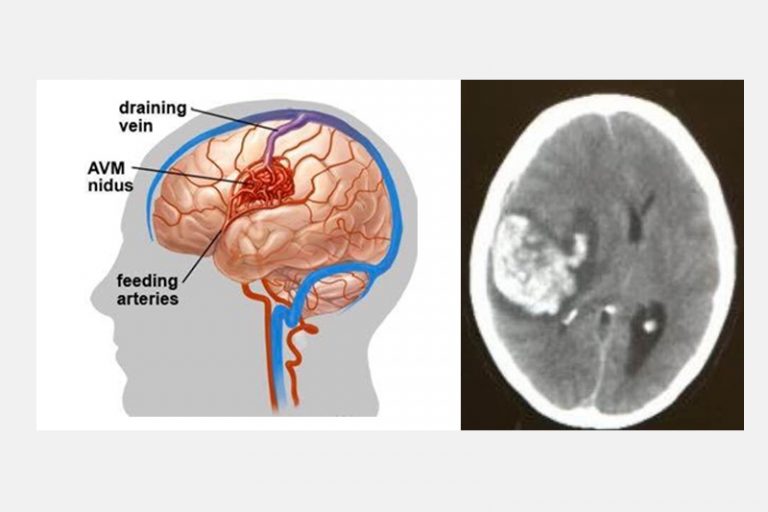

四歲小朋友,出生以來一切健康正常,沒有任何症狀,有一天隨著母親逛街,突然感到頭部劇痛,然後急速昏迷。送到醫院證實是先天性大腦動靜脈畸形血管瘤爆破而引致的嚴重出血性中風,他雖然從死亡鬼門關好不容易才被拯救出來,但即使經過多年的救治,也不能逆轉中風對大腦神經的永久損害,如今小孩仍然患有嚴重殘疾,不能與人溝通及需要長期臥床。

先天性大腦動靜脈畸形血管瘤爆破而引致的嚴重出血性中風